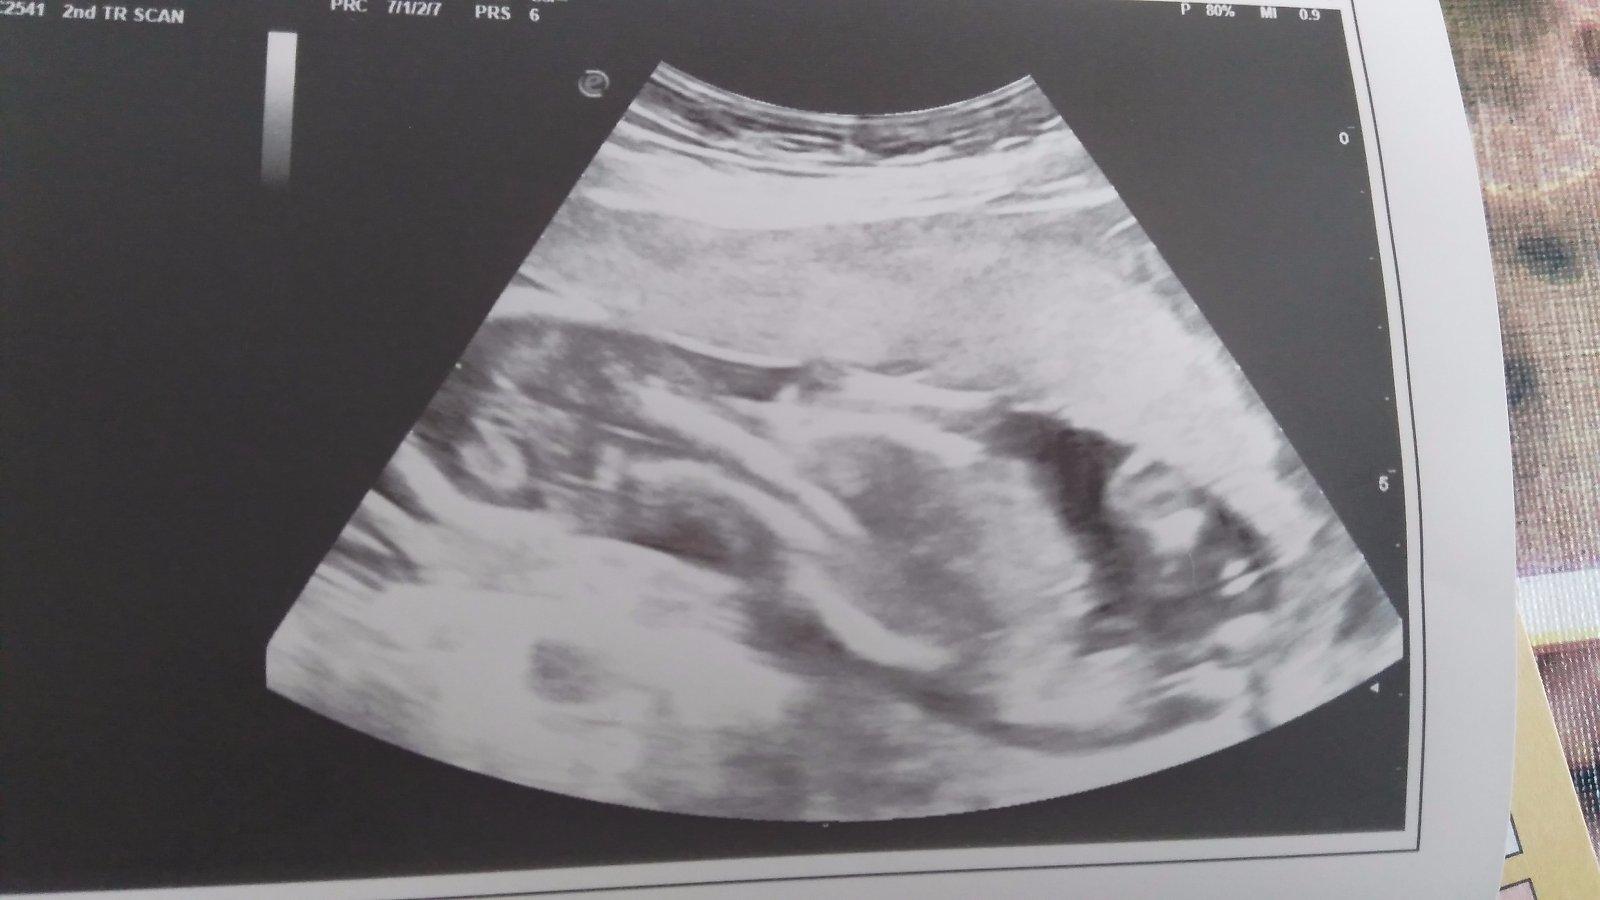

@ariana195195 my sa docela bojíme chlapca kvôli zvýšenému riziku autizmu. Keďže už synčeka s touto dg.mame. dievčatka postihuje maličké percento. No ja som na sone dnes videla kávové zrno, som 15+3, už by to mohlo tak aj zostať 🙂

@trblietava ja vidim.krasny dusik